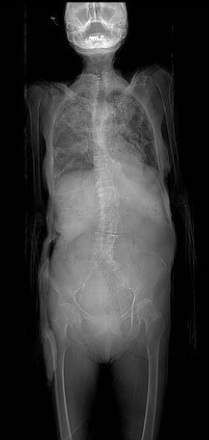

This is the scout film and CT scan of cadaver 33486, which shows a case of thoracic levoscoliosis (left convexity) and lumbar dextroscoliosis (right convexity). Look first at the anterior-posterior scout film to appreciate the curvature and make reference of where the major curves are, then look at the CT scan and watch the spine curve first to the left then the right as you scan from thoracic to lumbar vertebrae.